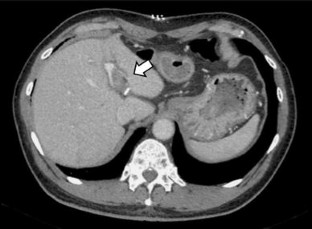

Patent ductus venosus (PDV) is a rare condition of a congenital portosystemic shunt from the umbilical vein to the inferior vena cava. This report presents the case of an adult patient with PDV, who was successfully treated with laparoscopic shunt division. A 69-year-old male was referred with hepatic encephalopathy. Contrast-enhanced CT revealed a large connection between the left portal vein and the inferior vena cava, which was diagnosed as PDV. The safety of a shunt disconnection was confirmed using a temporary balloon occlusion test for the shunt, and the shunt division was performed laparoscopically. The shunt was carefully separated from the liver parenchyma with relative ease, and then divided using a vascular stapler. Portal flow was markedly increased after the operation, and the liver function of the patient improved over the 3-month period after surgery. Although careful interventional evaluation for portal flow is absolutely imperative prior to surgery, a minimally invasive laparoscopic approach can be safely used for treating PDV.

Fig. 2